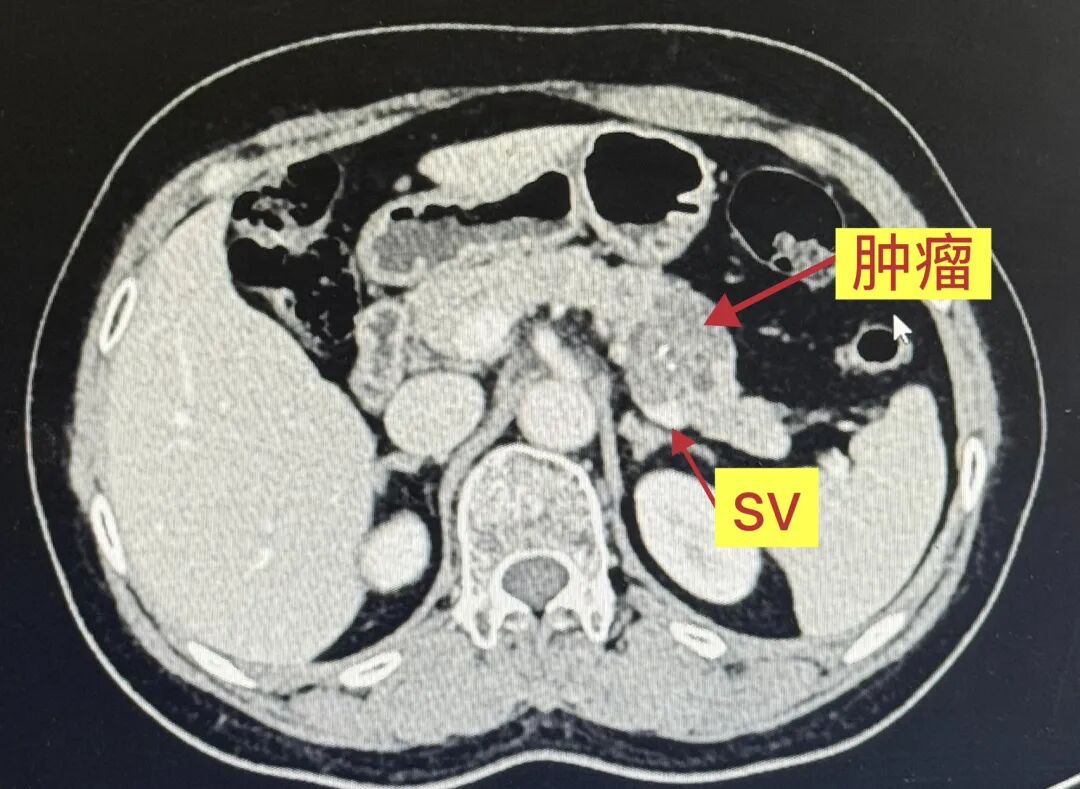

基本资料:患者为58岁女性,因“体检发现胰腺占位1月”入院,身体状况良好,BMI:22.5,CA199:5.5,增强CT提示胰尾3.5cm混杂低密度灶。

术前影像学评估及规划:MRI上呈多囊型、“蜂窝征”,中央钙化,我的初步印象符合SCN浆液性囊腺瘤“奶奶瘤”的表现。做Kimura还是Warshaw?CT增强看到肿瘤几乎将脾动静脉完全“吃”进去,但肿瘤距离LGA和SA在脾门的汇合点有一定距离。我知道Kimura很好,但在腔镜下剥离脾静脉带给我的多是一些不太美妙的回忆,而且从我做Warshaw的经验看,患者普遍恢复得不错。